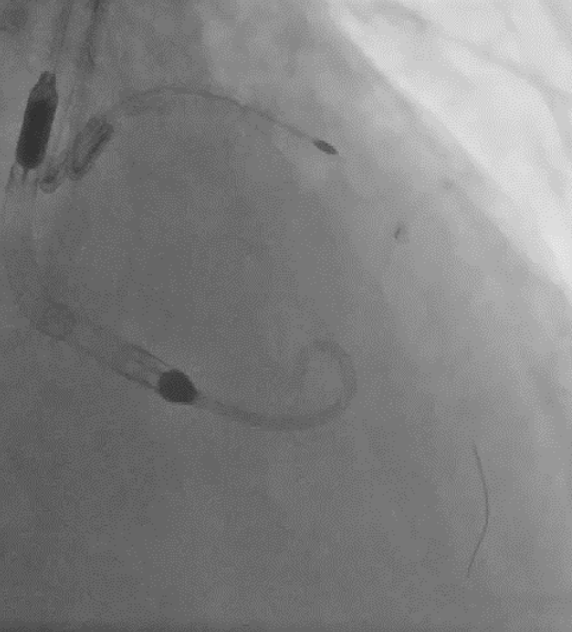

Coronary angiogram showed CTO in all 3 vessels. Impella assisted PCI was suggested in combined HEART team meeting in view of high surgical risk (STS score >8). Antegrade approach was adapted. LAD CTO was successfully crossed with Gaia Next 1 with Turnpike support. A 2.25x40mm stent was deployed to mid LAD and an overlapping 3.5x28mm stent was deployed to LM-LAD across wire protected LCx. Post dilatation was performed. Final IVUS and angiogram showed satisfactory result.

Upon removal of the workhorse wire from distal LAD, an unforeseen nightmare started. The wire tip entangled with the distal stent edge. Turnpike microcatheter was used to retrieve the stuck wire. Unfortunately, upon pullback, the wire fractured and only its proximal part was retrieved. The distal part remain stuck in the distal stent edge and uncoiled with filaments extending from stent edge into aorta. PingPong guiding was immediately set up. ClearStent showed distal stent edge deformity which rendered passage of any device including 1.0mm balloon impossible. In order to modify the obstructing stent struts at distal edge, it was decided to use rotablation. Direct wiring across the deformed distal stent edge with rota wire was successful. Pecking motion of rotablation was performed with the aim to clear the obstructing scaffolds. After 25 runs at high speed with 1.5bur, the deformed distal stent was successfully crossed. The trapped wire tip was unexpectedly released and fell into the septal branch. The fractured filaments were assessed with IVUS and ClearStent. Subsequently, the filaments were all retrieved with 2 twisting wires. IVUS confirmed complete clearance of any filament. The LM-LAD stent was again post dilated and optimized. Final angiogram and follow up restudy 4months later both showed satisfactory result with patent stents.